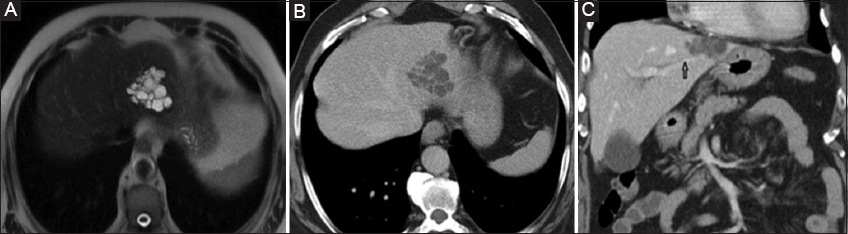

In type 4 IPNBs, mucin overproduction leads to increased intraductal pressure and aneurysmal biliary dilation or cystic dilation of peribiliary glands [7,42]. These cystic-type IPNBs present as multilocular cystic masses with a “bunch of grapes” appearance and enhancing mural nodules (Fig. 3). Type 4 IPNBs, which closely resemble MCNs, can be differentiated on the basis of communication between the cystic lesion and the bile ducts, best depicted on MRCP sequences [2,31]. Similarly, MCNs in contrast to cystic-type IPNBs are not accompanied by biliary dilation. Gadolinium-based agents, excreted into the lesion on the hepatobiliary phase, are quite helpful in this regard [31,42]. Apart from MCNs, the differential diagnosis should include complicated hepatic cysts, localized Caroli disease, and more rare cystic hemangiomas, lymphangiomas, hepatic foregut cysts, mesenchymal hematomas or teratomas [1,31].

thumblarge

Figure 3 (A) T2-weighted axial magnetic resonance imaging: a well-defined multilocular “bunch of grapes-type” intrahepatic mass is depicted, containing high intensity fluid content and multiple internal septa. (B) Axial contrast enhanced computed tomography (CT): the multilocular cystic lesion shows thick internal septa with persistent delayed phase enhancement. (C) Coronal portal phase CT: a well-defined multilocular cystic mass is depicted in the left liver lobe. This is in close proximity to the hypodense linear left intrahepatic biliary duct (arrow)